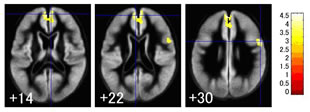

収縮期血圧(値が大きい方)が高くなると、後頭葉に黄色で示した小さな場所に萎縮が見つかります。飲酒も脳萎縮の原因になっているようです。飲酒量が多い人ほど、前頭葉上部の中前頭回と呼ばれる場所に大きな萎縮が見つかります。

収縮期血圧(高いほうの血圧)が高くなると、後頭葉が萎縮しやすい。黄色に見えるところが、より萎縮の進んでいるところ

お酒をたくさん飲むと、前頭葉上部が萎縮します(数字は脳断面のレベル)黄色に見えるところが、より萎縮の進んでいるところ